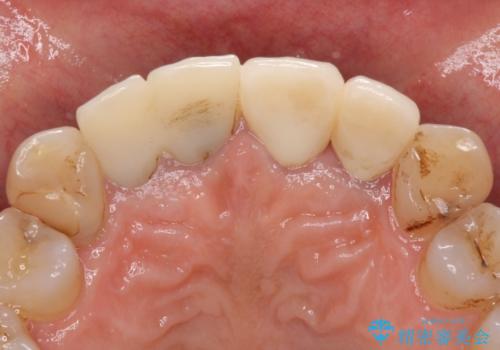

- 昨年治療した前歯の根尖部に痛みを感じ、ラバーダムや顕微鏡を用いた根管治療を希望されて、転院された患者様です。

前医にて神経を取り除いた処置を行った際、ラバーダムが使用されなかったとのことで転院されてきました。

根管治療を実施した後、オールセラミッククラウンに補綴することとしました。